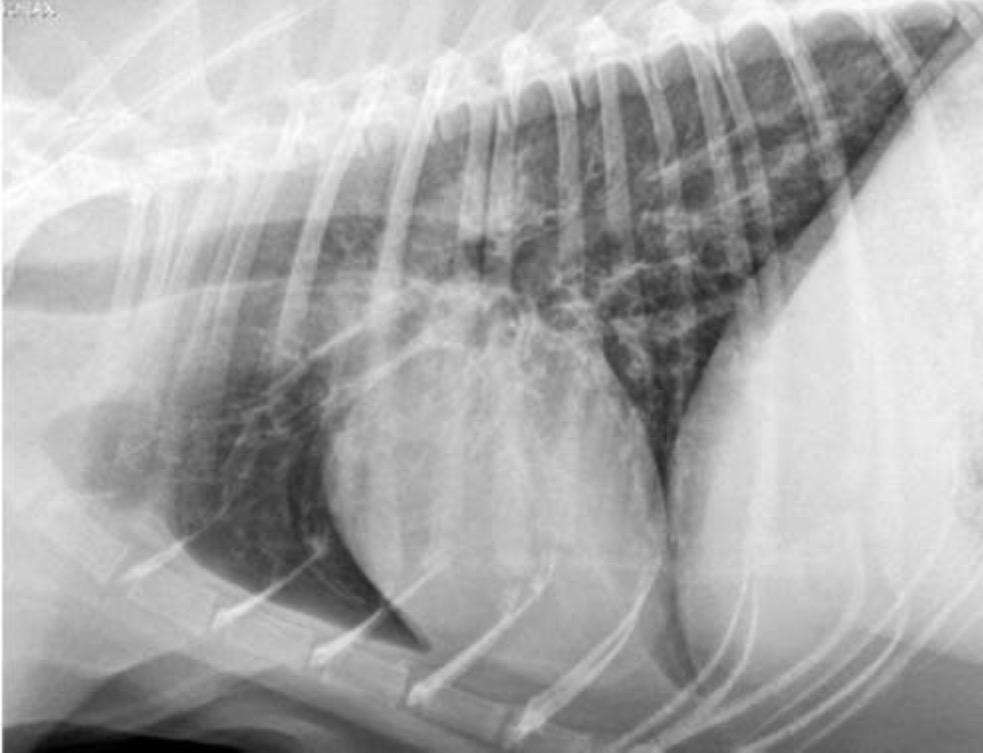

What type of pattern can be seen in this radiograph?

Bronchial → see rings + railroad tracks